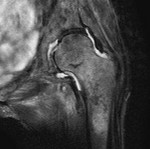

[画像診断]大腿骨頚部不全骨折について 2011-02-10